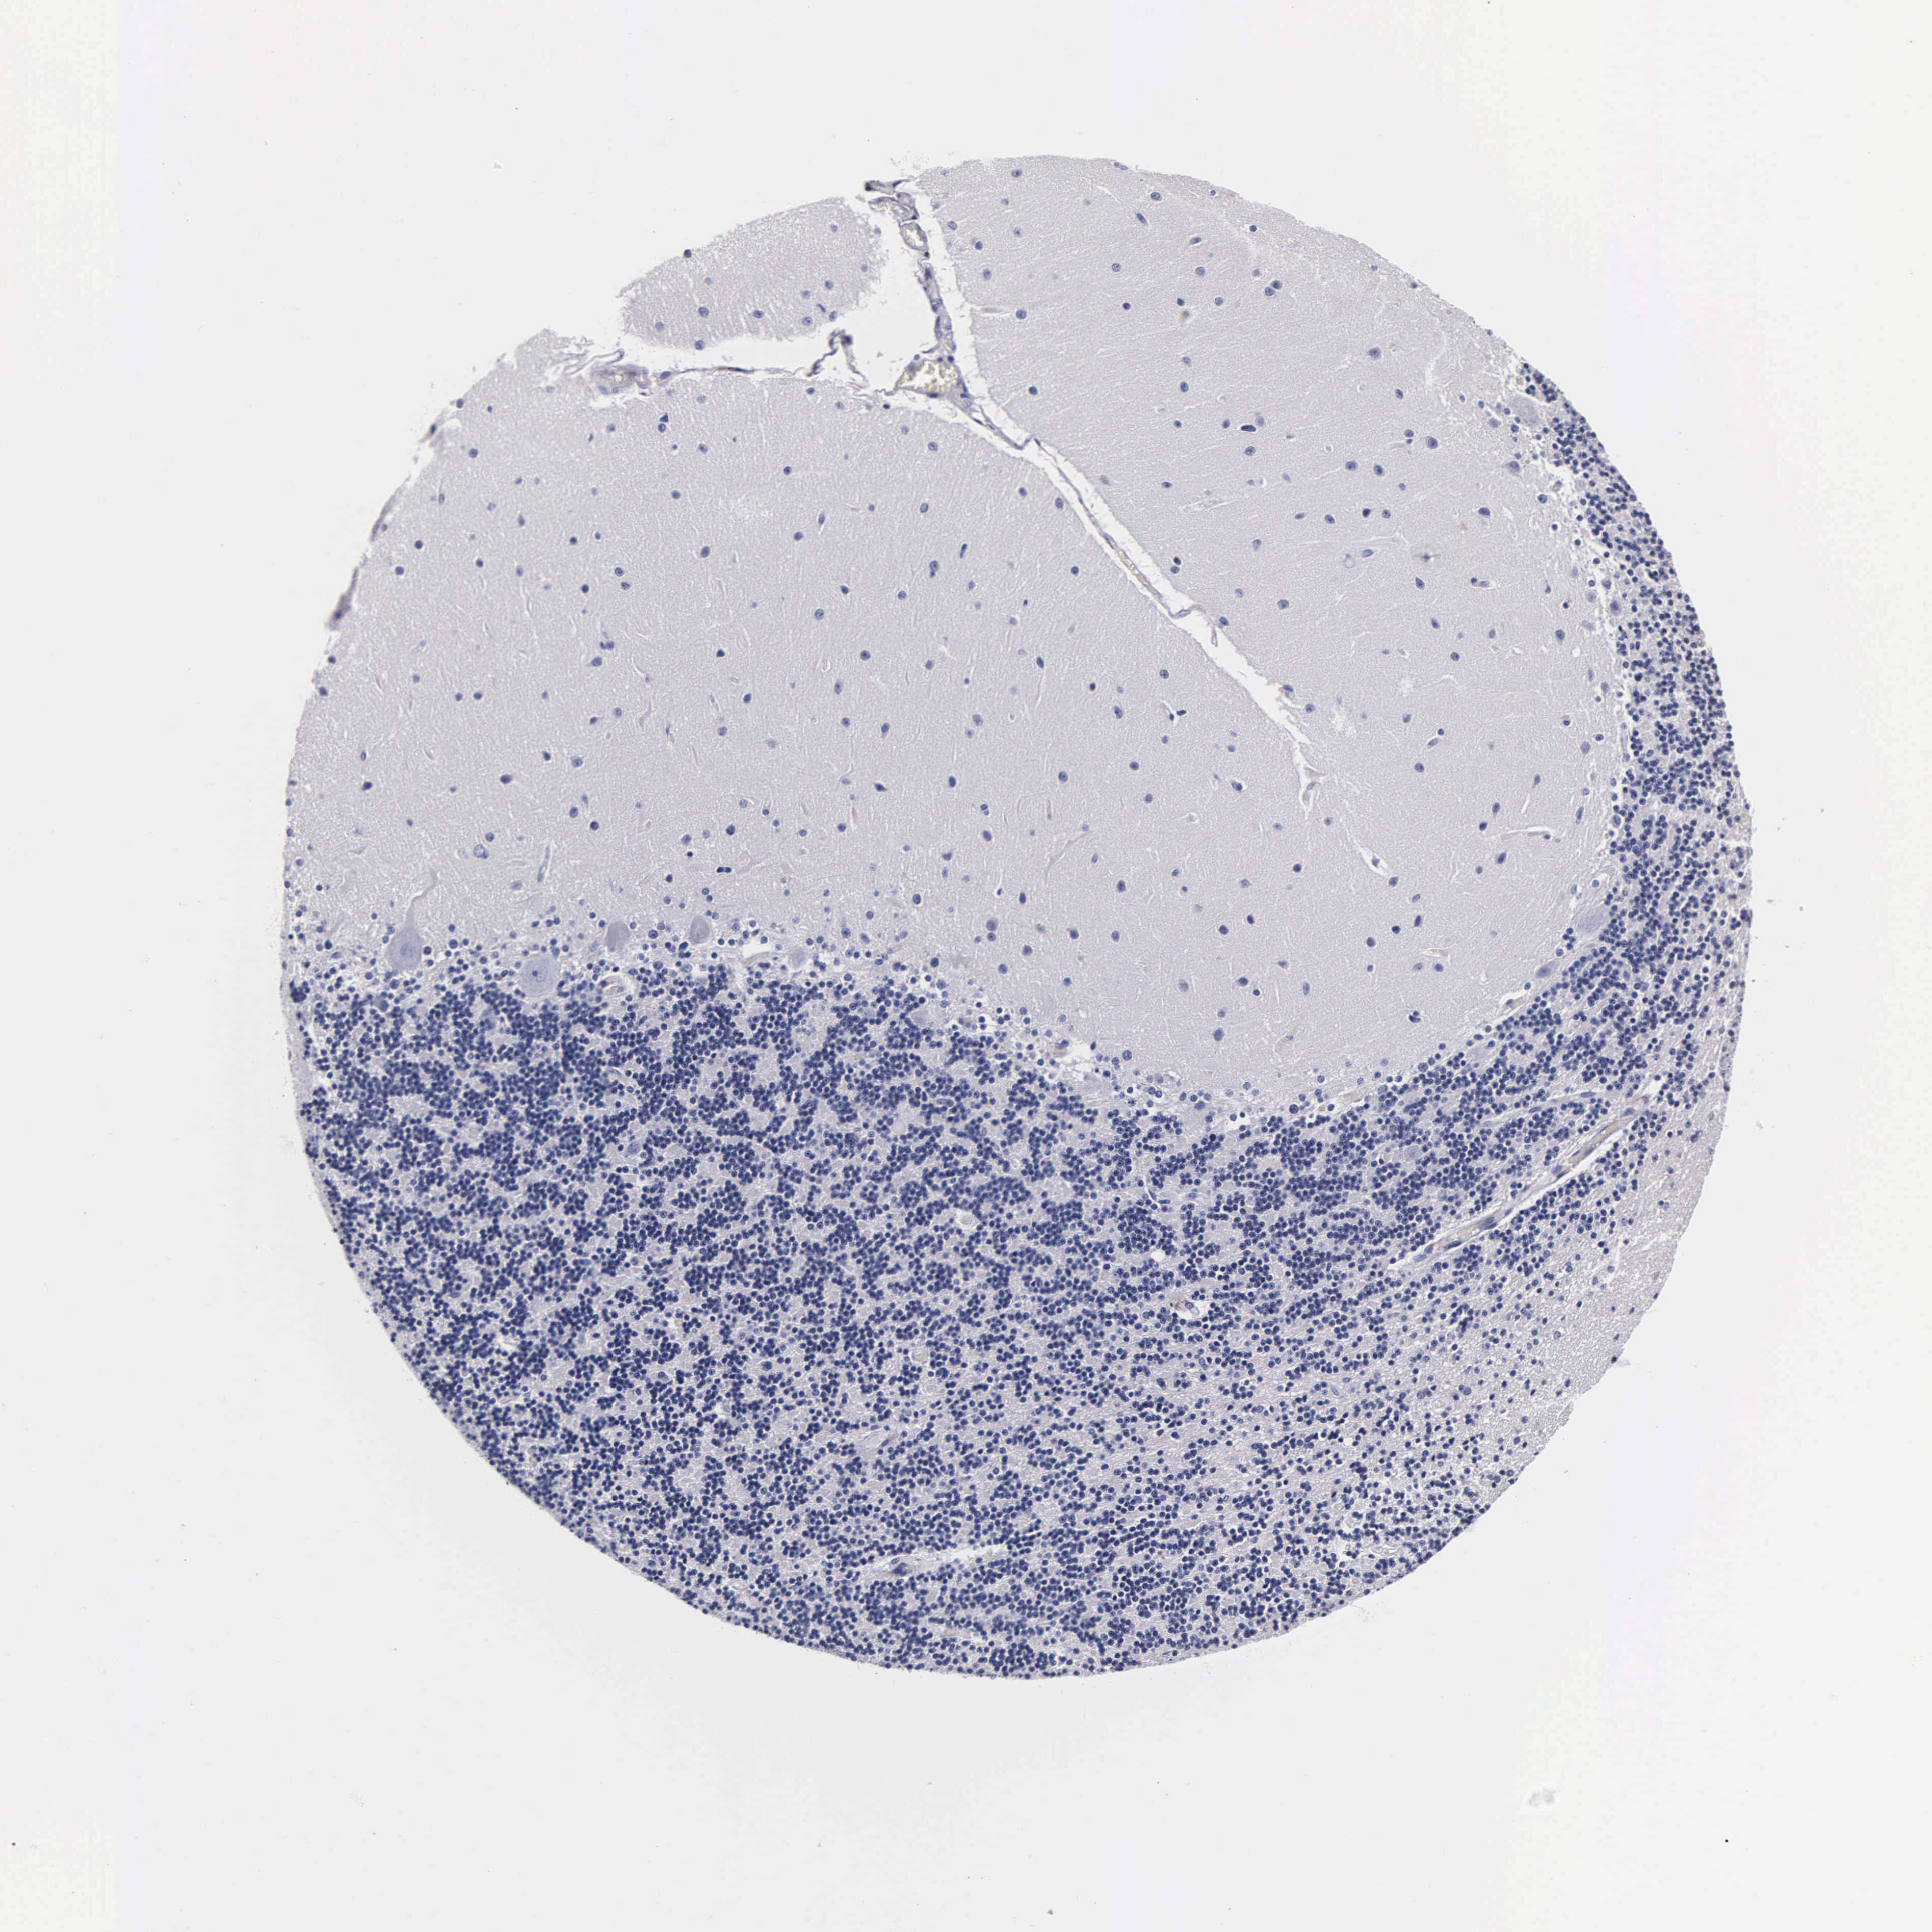

CEREBELLUM - Antibody stainingi

Antibody staining in the annotated cell types in the current human tissue is reported as not detected, low, medium, or high, based on conventional immunohistochemistry profiling in selected tissues. This score is based on the combination of the staining intensity and fraction of stained cells.

Each image is clickable and will lead to virtual microscopy that enables deeper exploration of all samples and also displays staining intensity scores, fraction scores and subcellular localization as well as patient and tissue information for each sample.

Antibody HPA004932Antibody CAB000048Antibody CAB012098Antibody CAB053843

Purkinje cells Not detectedNot detectedMediumNot detected

Cells in granular layer Not detectedNot detectedNot detectedNot detected

Cells in molecular layer Not detectedNot detectedNot detectedNot detected